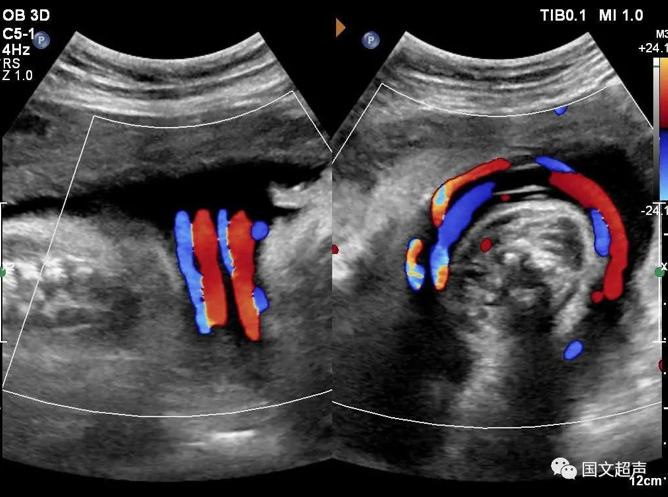

四.關(guān)于臍帶繞頸

臍帶有補(bǔ)償性伸展,纏繞松弛對胎兒影響不大,但如果纏繞過緊可影響胎兒血供,有造成胎心率改變、胎兒缺氧、窒息甚至胎死宮內(nèi)的風(fēng)險。

實(shí)際上影響胎兒預(yù)后的主要因素不在于繞頸的周數(shù),而在于除去繞頸所剩的臍帶長度。如果孕媽媽只繞頸一周但臍帶相對過短,仍可造成不良結(jié)局。

臍帶繞頸的孩子很多,但發(fā)生不良結(jié)局的確占少數(shù),所以不必過度擔(dān)心,只要每天的胎動正常,沒有突然的增多和減少,定期復(fù)查即可。